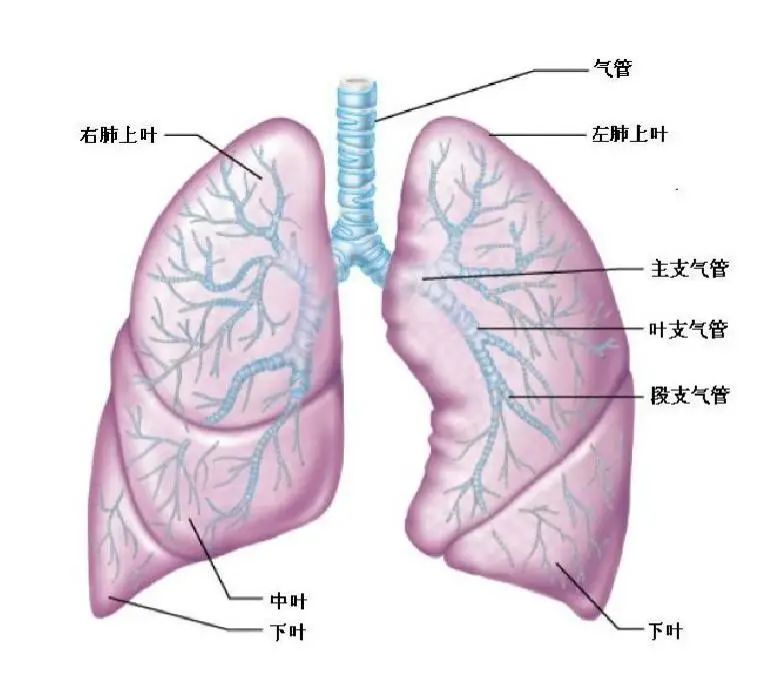

肺癌手术切哪里?切多少?

肺癌手术切哪里?切多少?

【术前谈话】肺是怎样的器官?胸腔镜手术是怎么做的?...

【术前谈话】肺是怎样的器官?胸腔镜手术是怎么做的?...